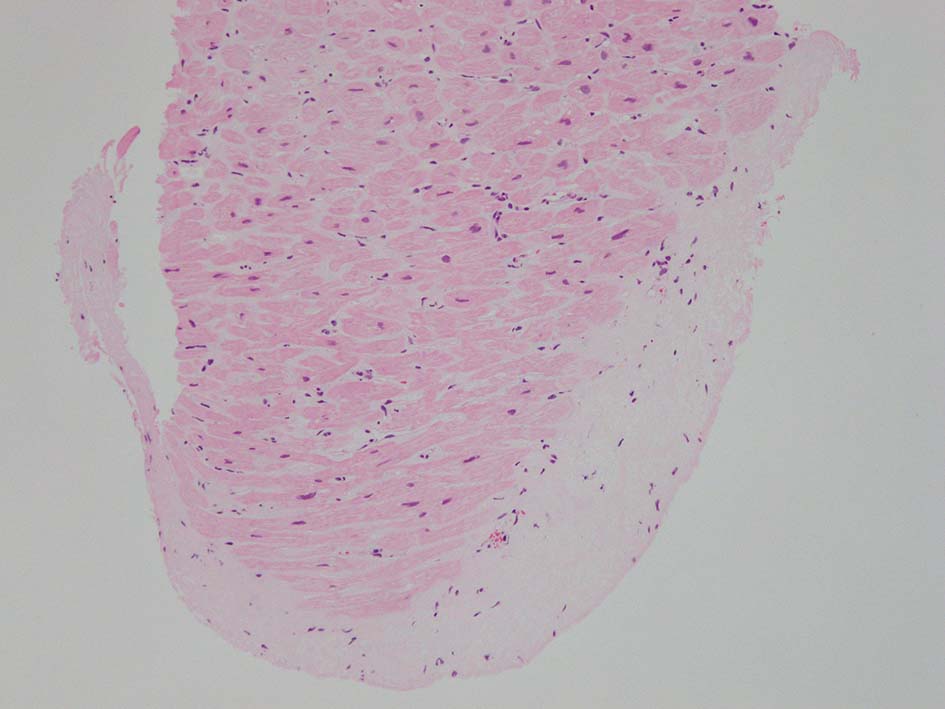

HE所見では, 明瞭な沈着物はわかりにくい. 血管壁が確認できる血管も少ない. congo-red染色で沈着が考えられる所見があり, 簡易偏光で(みずらいけれど)apple-greenの偏光があるように見える.(サムネイルのクリックで大きな画像が見られます)